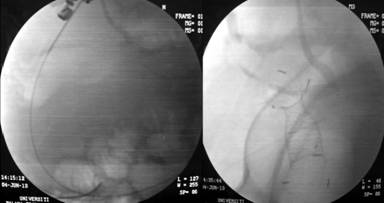

Unfortunately, she was admitted two weeks later with fever, melena and coffee ground vomiting. Her blood pressure was 80/50 mmHg, pulse was 120 beat per minute and her hemoglobin dropped to 7.6 g/dL. EGD revealed massive blood clots in the stomach and although the stent was in situ, there were clots seen within the stent which suggested that the source of bleeding was from the cystic cavity. She was referred for angiography and embolization; angiogram showed bleeding from a ruptured splenic artery pseudoaneurysm. Coil embolization (Figure 5) was carried out successfully and patient’s vital signs improved immediately. She was discharged well a few days later.

Figure 5. Angiography showing splenic artery pseudoaneurysmal bleed (left) followed by coil embolization (right). |